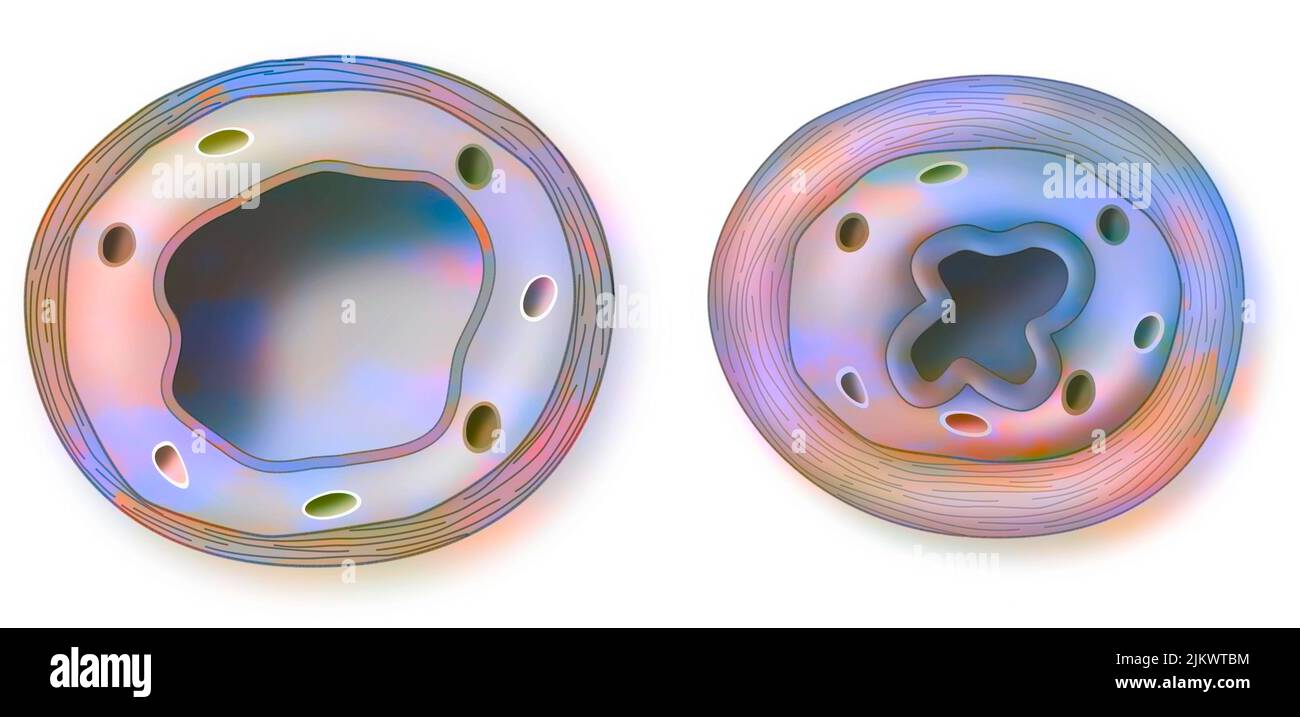

RF2JKWPFG–Pourquoi utiliser la triple thérapie: Pour essayer d'arrêter le développement de la maladie du SIDA.